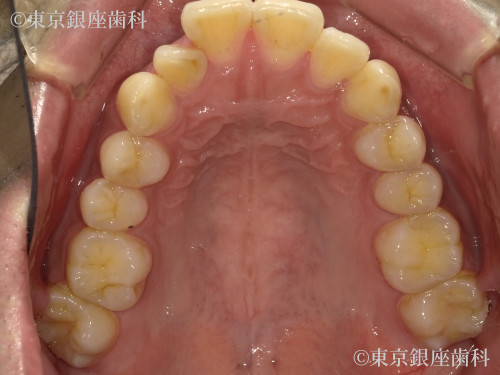

After

インビザライン:ライトパッケージ

側方前突